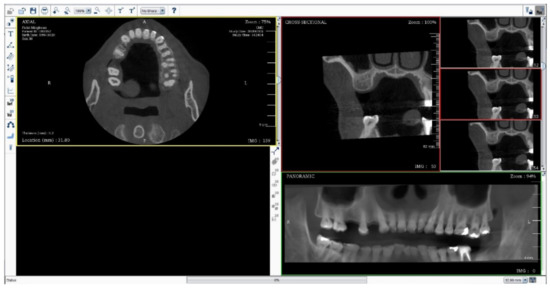

A total of 316 images were then anonymously captured to ensure that no private information was revealed. The full-screenshot images were taken from DTP software with the joint photographic expert group (JPEG) format at 1920 × 1080 pixels with 24-bit depth (Figure 1). Three hundred images were used for model training, which were randomly sorted from 1–300 to create six data sets, including 1–50, 1–100, 1–150, 1–200, 1–250, and 1–300. These six data sets were called the training set. The remaining 16 images were selected for accuracy testing to assess the performance of the developed model; this set of 16 images was called the testing set.

The six original training sets were separately uploaded into the IBM PowerAI Vision platform (IBM Thailand Co., Ltd., Bangkok, Thailand), then the labelling process for model training was applied within the GUI of the platform. This user-defined data is significant for describing the desired output data.

The labelled area in each image was generated in a square shape by connecting the four lines from the farthest border of the alveolar bone available for implant placement. The mentioned four lines included the upper border, lower border, mesial border, and distal border in a panoramic image, together with the upper border, lower border, buccal border, and lingual border in a cross-sectional image. The demonstration of the labelling process is displayed in Figure 2 and Figure 3a.

Subsequently, each labelled area was then annotated with eight different sets, including 4.2 × 8, 4.2 × 10, 4.2 × 12, 5.0 × 8, 5.0 × 10, 5.0 × 12, Int SFE, and Lat SFE for each panoramic and cross-sectional image. The annotations for both panoramic and cross-sectional images were independent because of their own characteristics, and they were indicated with the corresponding labelled box area (as displayed in Figure 3a).

Thereafter, the six original training sets and the new 24 augmented training sets were then utilized to train the AI. The faster R-CNN algorithm was used to develop the AI. The model hyperparameters were configured with the default setting. After 30 training sets were completely trained, the trained model was then deployed and evaluated with the 16 prerequisite images in the testing set which included 2 images of every picture that must be indicated to 4.2 × 8, 4.2 × 10, 4.2 × 12, 5.0 × 8, 5.0 × 10, 5.0 × 12, Int SFE, and Lat SFE. Each testing image was annotated as the ground truth. The testing process required uploading each image one at a time, and the deployed model then displayed the detection with bounding boxes, annotation, and confidence percentage. Each testing image that was uploaded into the deployed model was not included in the development of the model. An example of the testing process is demonstrated in Figure 3b. If the labelled object in the images was indicated with more than an 80% confidence threshold, the annotation results were then recorded throughout the study. The recorded data were analyzed for detection and accuracy. Detection was defined as the event resulting in object detection, and accuracy was defined as the matching outcome between the annotation of the resulting object detection and the actual outcome that was interpreted by the human developer.

Figure 1. The full screen image capture of DentiPlan Pro version 3.7.

Applsci 11 10159 g001